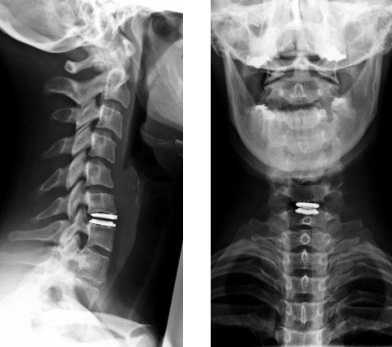

Является редкой практикой. Выполняется в детском возрасте в случае доказанных аномалий строения. Во взрослой практике чаще выполняется операция «спондилодез». Она заключается в имплантации конструкции из металлических пластин и фиксирующих элементов. Её задача — препятствовать избыточной подвижности позвоночника. Операция применяется после травм, дискотомий и ламинэктомий. Последние две проводятся при грыжах позвоночника.